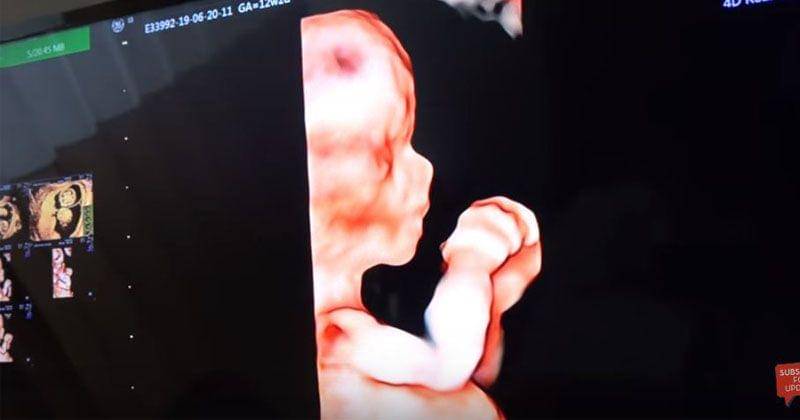

4. Melakukan USG 4D

Untuk mendapatkan hasil yang maksimal, Ammar dan Irish memilih untuk melakukan USG 4D. Dengan melakukan USG 4D, mereka bisa melihat tubuh janin secara keseluruhan.

Termasuk bisa melihat bagian tubuh janin seperti mulut dan hidung. Dengan menggunakan pemeriksaan USG 4D, maka akan lebih banyak pula detail yang bisa dilihat dari berbagai sudut, sehingga bisa turut membantu mendiagnosis kondisi seperti misalnya bibir sumbing.

Dengan USG 4D, Ammar dan Irish pun dapat melihat hidung mancung calon bayi mereka.

"Hidungnya udah keliatan, mancung lagi," ungkap Ammar saat melihat hasil USG 4D.

Selain itu, pemeriksaan USG 4D juga bisa dilihat dokter untuk memeriksa jantung dan organ internal lainnya. Oleh sebab itu, dokter pun bisa menggunakan pemeriksaan USG 4D untuk keperluan medis saat diperlukan.